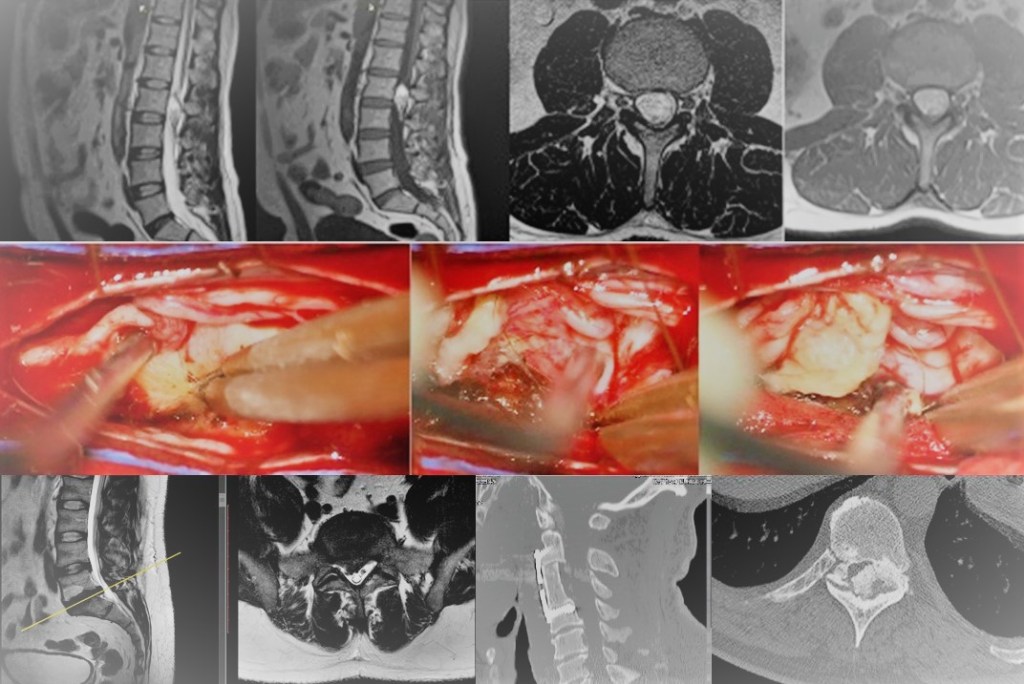

- En cuanto a los tumores que afectan a las cubiertas o elementos de sostén de las estructuras neurológicas, los más frecuentes son los meninigomas, derivados de las capas meningeas que recubren la médula espinal, asi como las schwannomas o neurinomas originados en las células de sostén de raices nerviosas. En ambos casos puede tener lugar la compresión de la médula espinal que provoque la pérdida de función de la misma con el desarrollo de una pérdida de sensibilidad y/o movilidad, asi como posible alteración del control de los esfínteres. Para su tratamiento contamos con la posibilidad de monitorización neurofisiológica intraoperatoria y Microcirugía.

- Por ultimo, lo tumores propiamente intramedulares se albergan en el interior de la médula espinal provocando además de dolor, la disfunción de la misma con la aparicion de alteraciones en la sensibilidad, esfinteres y fuerza en extremidades. Están representados fundamentalente por los astrocitomas y los ependimomas, lesiones aunque muy infrecuentes, altamente complejas precisando de tratamientos individualizados, de alta precisión y con empleo de herramientas como Microcirugía, Monitorización neurofisiológica intraoperatoria y enfoque interdisciplinar.

-Tumores espinales: Dan lugar a una gran variedad de situaciones debido a que pueden afectar a diferentes compartimentos: óseo (tumores primarios ó metástasis con o sin extensión al canal raquídeo; siendo los hemangiomas los más frecuentes), intradural-extramedular (los más frecuentes meningiomas y algunos neurinomas) e intradural-intramedular (astrocitomas y ependimomas). Suelen manifestarse con dolor, alteración de la sensibilidad y/o fuerza en las extremidades acompañada o no de alteración esfinteriana. Van a precisar cirugía en caso de que generen inestabilidad vertebral, déficit neurológico o muestren un comportamiento agresivo.

- Laminectomía: En este caso la exposicion de los elementos vertebrales posteriores se lleva a cabo de forma bilateral para lograr la extirpación de elementos óseos y ligamentosos hiertróficos que están invadiendo el canal espinal reduciendo significativamente su diámetro y comprometiendo a las estructuras neurológicas contenidas en el mismo: médula espinal y/raíces nerviosas, según el segmento afectado. Puede llevarse a cabo en los segmentos lumbar, dorsal o cervical generalmente con incisiones ligeramente mayores a las empleadas en la microdiscectomía. Este procedimiento, además de para la liberación de los elementos neurológicos debida a la compresión artrósica de los mismos, es también el empleado comúnmente para acceder al canal espinal en caso de que sea necesaria la extirpa ión de tumores, evacuación de hemorragias o infecciones albergadas en dicho nivel.